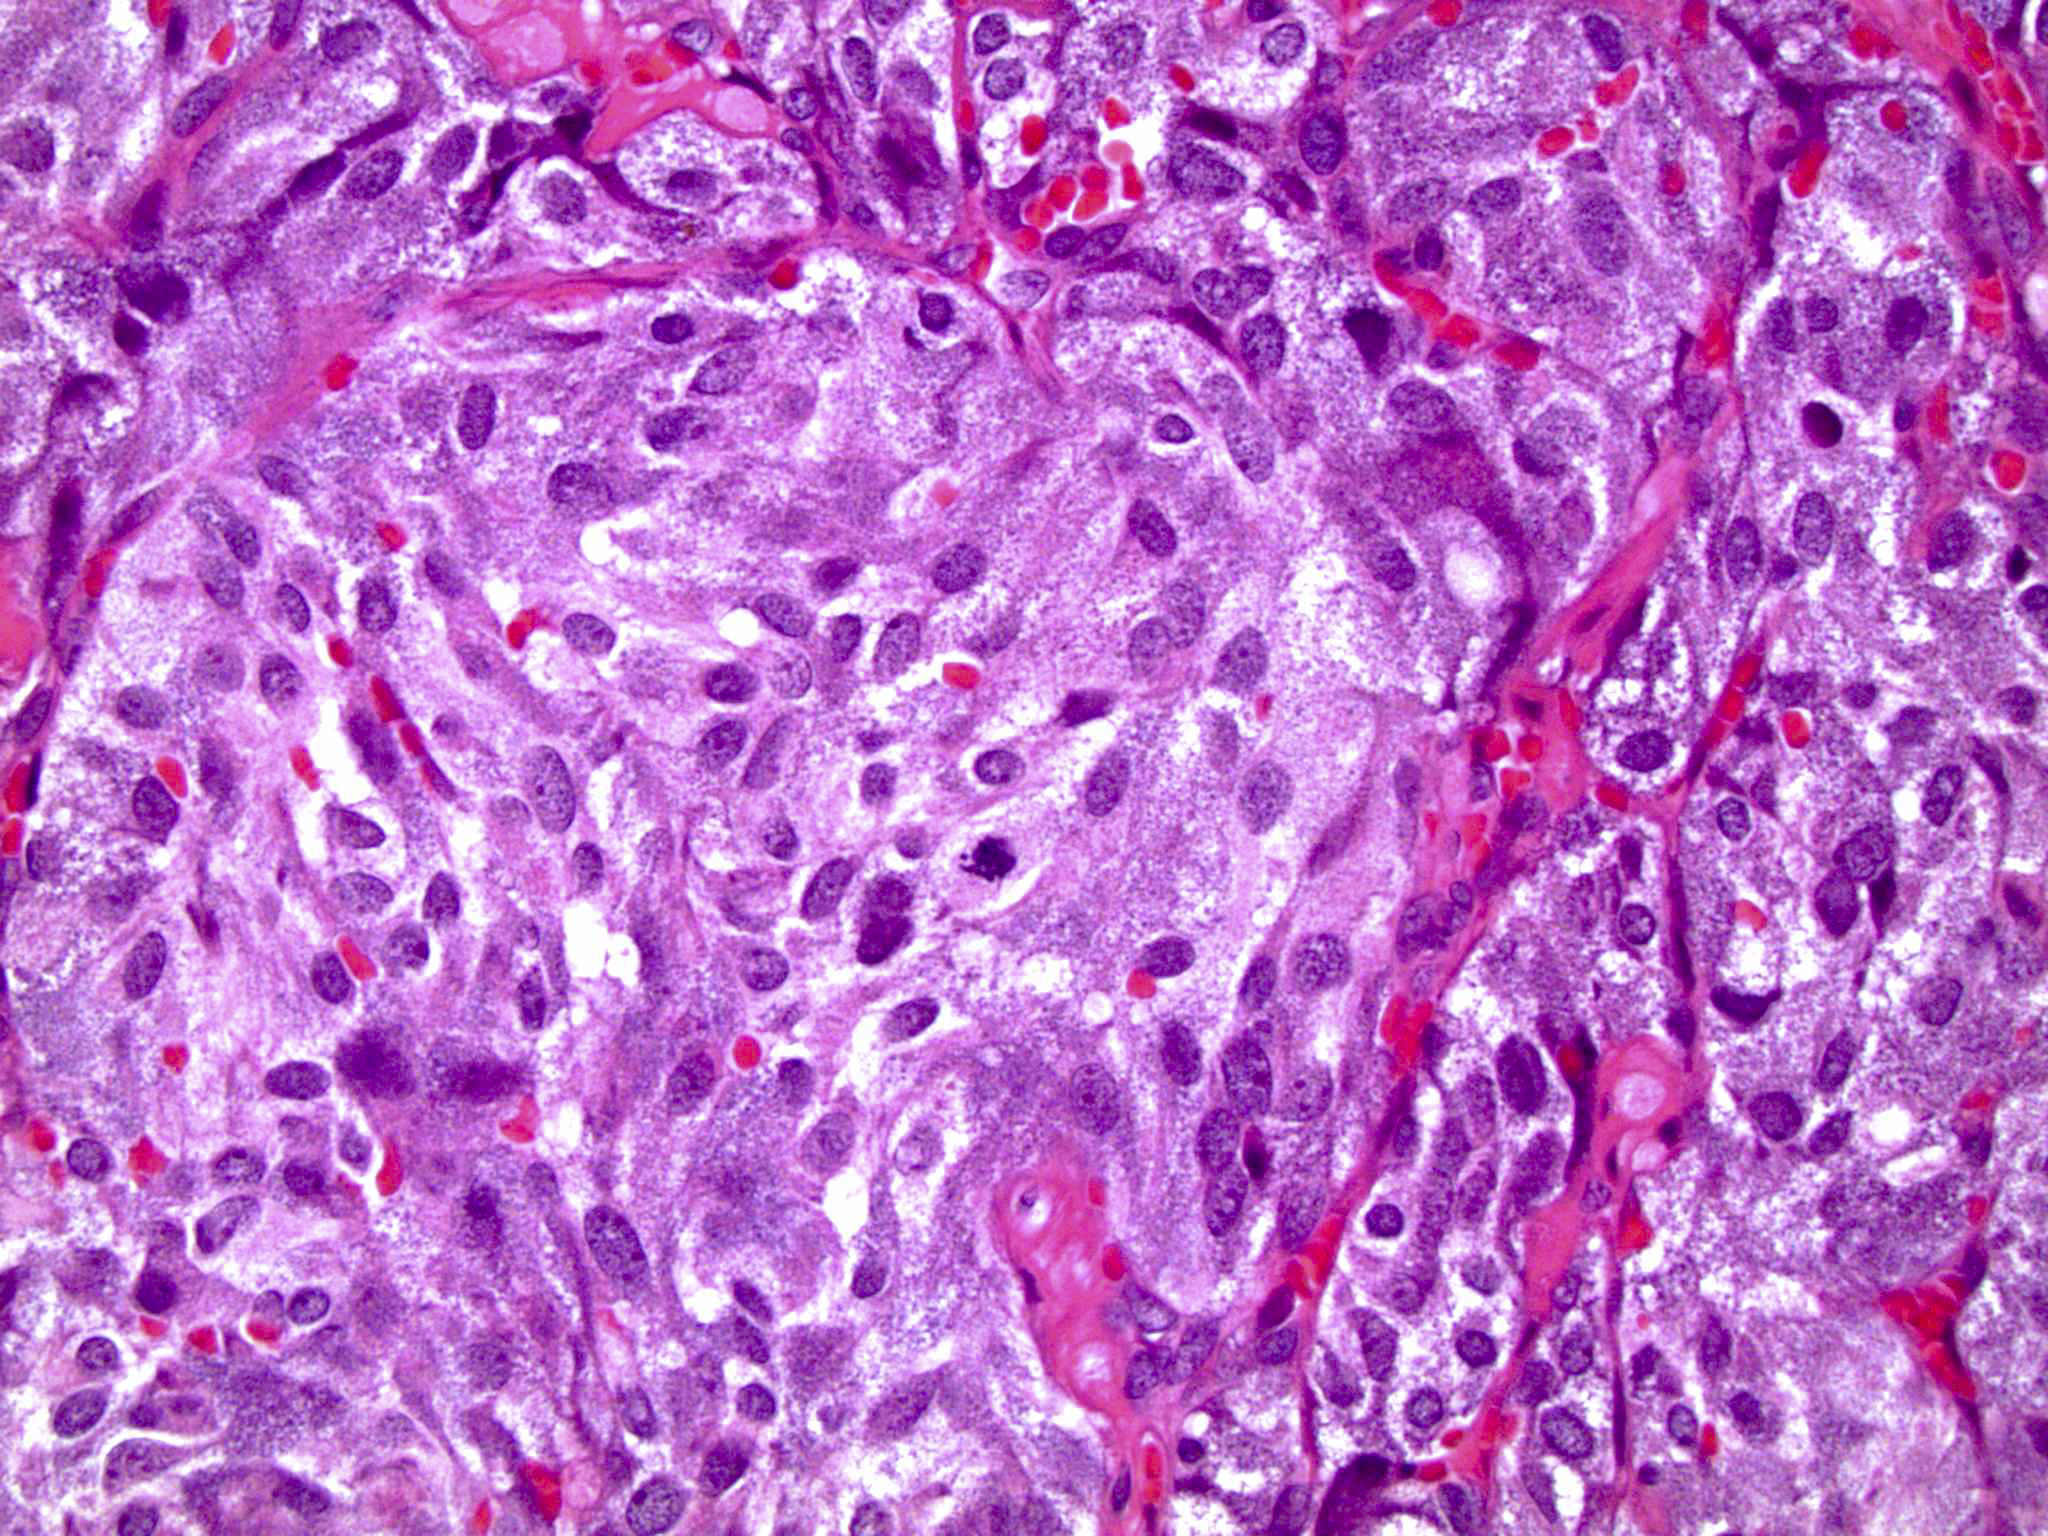

Microscopic (histologic) description

- Typical morphology: epithelioid cells with abundant, eosinophilic / amphophilic, granular cytoplasm and round / ovoid, vesicular / salt and pepper nuclei, arranged in a nested / zellballen pattern and separated by fibrovascular septae with sustentacular cells (Am J Surg Pathol 2004;28:94, World J Clin Cases 2014;2:591, Endocr Pathol 2022;33:90)

- May have focal pleomorphism, nuclear hyperchromasia, low mitotic activity or clear cytoplasm

Microscopic (histologic) images

Contributed by Theodorus H. van der Kwast, M.D., Ph.D., Michelle R. Downes, M.D., Debra L. Zynger, M.D. and David Cohen, M.B.B.Ch., M.D.

- Microscopic description: This specimen shows an unencapsulated, monomorphous population of round tumor cells in a nested / zellballen pattern with delicate vascular septa and intervening extravasated red blood cells. It predominantly involves the lamina propria of the bladder but in 1 tissue piece clearly involves muscularis propria. The tumor cells have abundant amphophilic cytoplasm and vesicular chromatin with occasional small nucleoli. There is no necrosis, diffuse growth pattern or vascular space invasion identified. The mitotic count is (maximally) 1/10 high power fields. Immunohistochemistry shows the tumor cells to be positive for GATA3 with strong and diffuse expression of synaptophysin and chromogranin, as well as retention of SDHB staining. The tumor cells are negative for AE1 / AE3, HMWK and p63. The Ki67 proliferation index is < 1%. S100 shows faint nuclear and cytoplasmic staining with occasional sustentacular cells identified.

- Microscopic description: Sections show unremarkable surface urothelium with a lesion in the deep lamina propria comprised of large eosinophilic cells with hyperchromatic, focally enlarged nuclei with occasional intranuclear inclusions. A fine vascular plexus is identified in some areas. Necrosis and hemorrhage are not identified. Mitotic rate = 1/10 high power fields (field of view [FOV] = 0.55 mm). The lesion extends to the cauterized base of the specimen. Immunostains confirm the lesion expresses synaptophysin, chromogranin and GATA3. SDHB is retained. AE1 / AE3, CD45, p63 and NKX3.1 are negative.